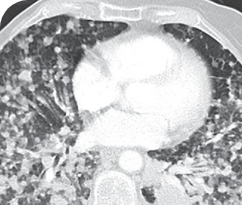

Response in primary and metastatic lesions1

Lung imaging of primary tumors.

SCAN 1: LUNG

SCAN 2: LUNG AND BONE

Images courtesy of Dr Maximilian Hochmair.